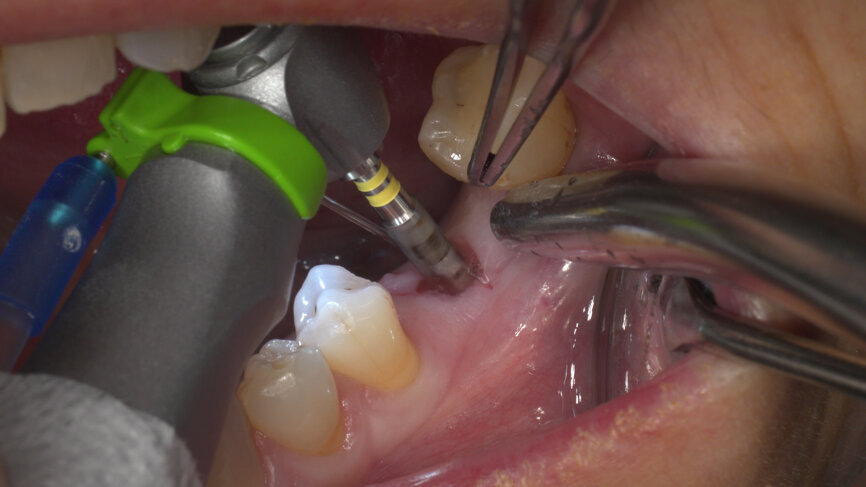

Under local anaesthesia, a flapless implant surgery technique was performed in position #36. Owing to the quality of the bone, staged drilling with continuous saline irrigation was performed in order to obtain a proper, safe insertion torque (Figs. 2–7). One implant (BLT, Regular Neck, Roxolid, ⌀ 4.8 × 10.0 mm) was placed, and a torque of 42 N cm was applied (Figs. 8–11).

The ISQ level was determined with the Osstell unit. After connecting a Type 54 SmartPeg, a score of 82 was obtained (Fig. 12). The decision to employ an immediate loading protocol has to take account of the surgeon’s personal experience and skills, the insertion torque value, the ISQ levels and the medical and dental characteristics of the patient. In this case, all these parameters were evaluated as excellent, and the immediate loading protocol was selected.